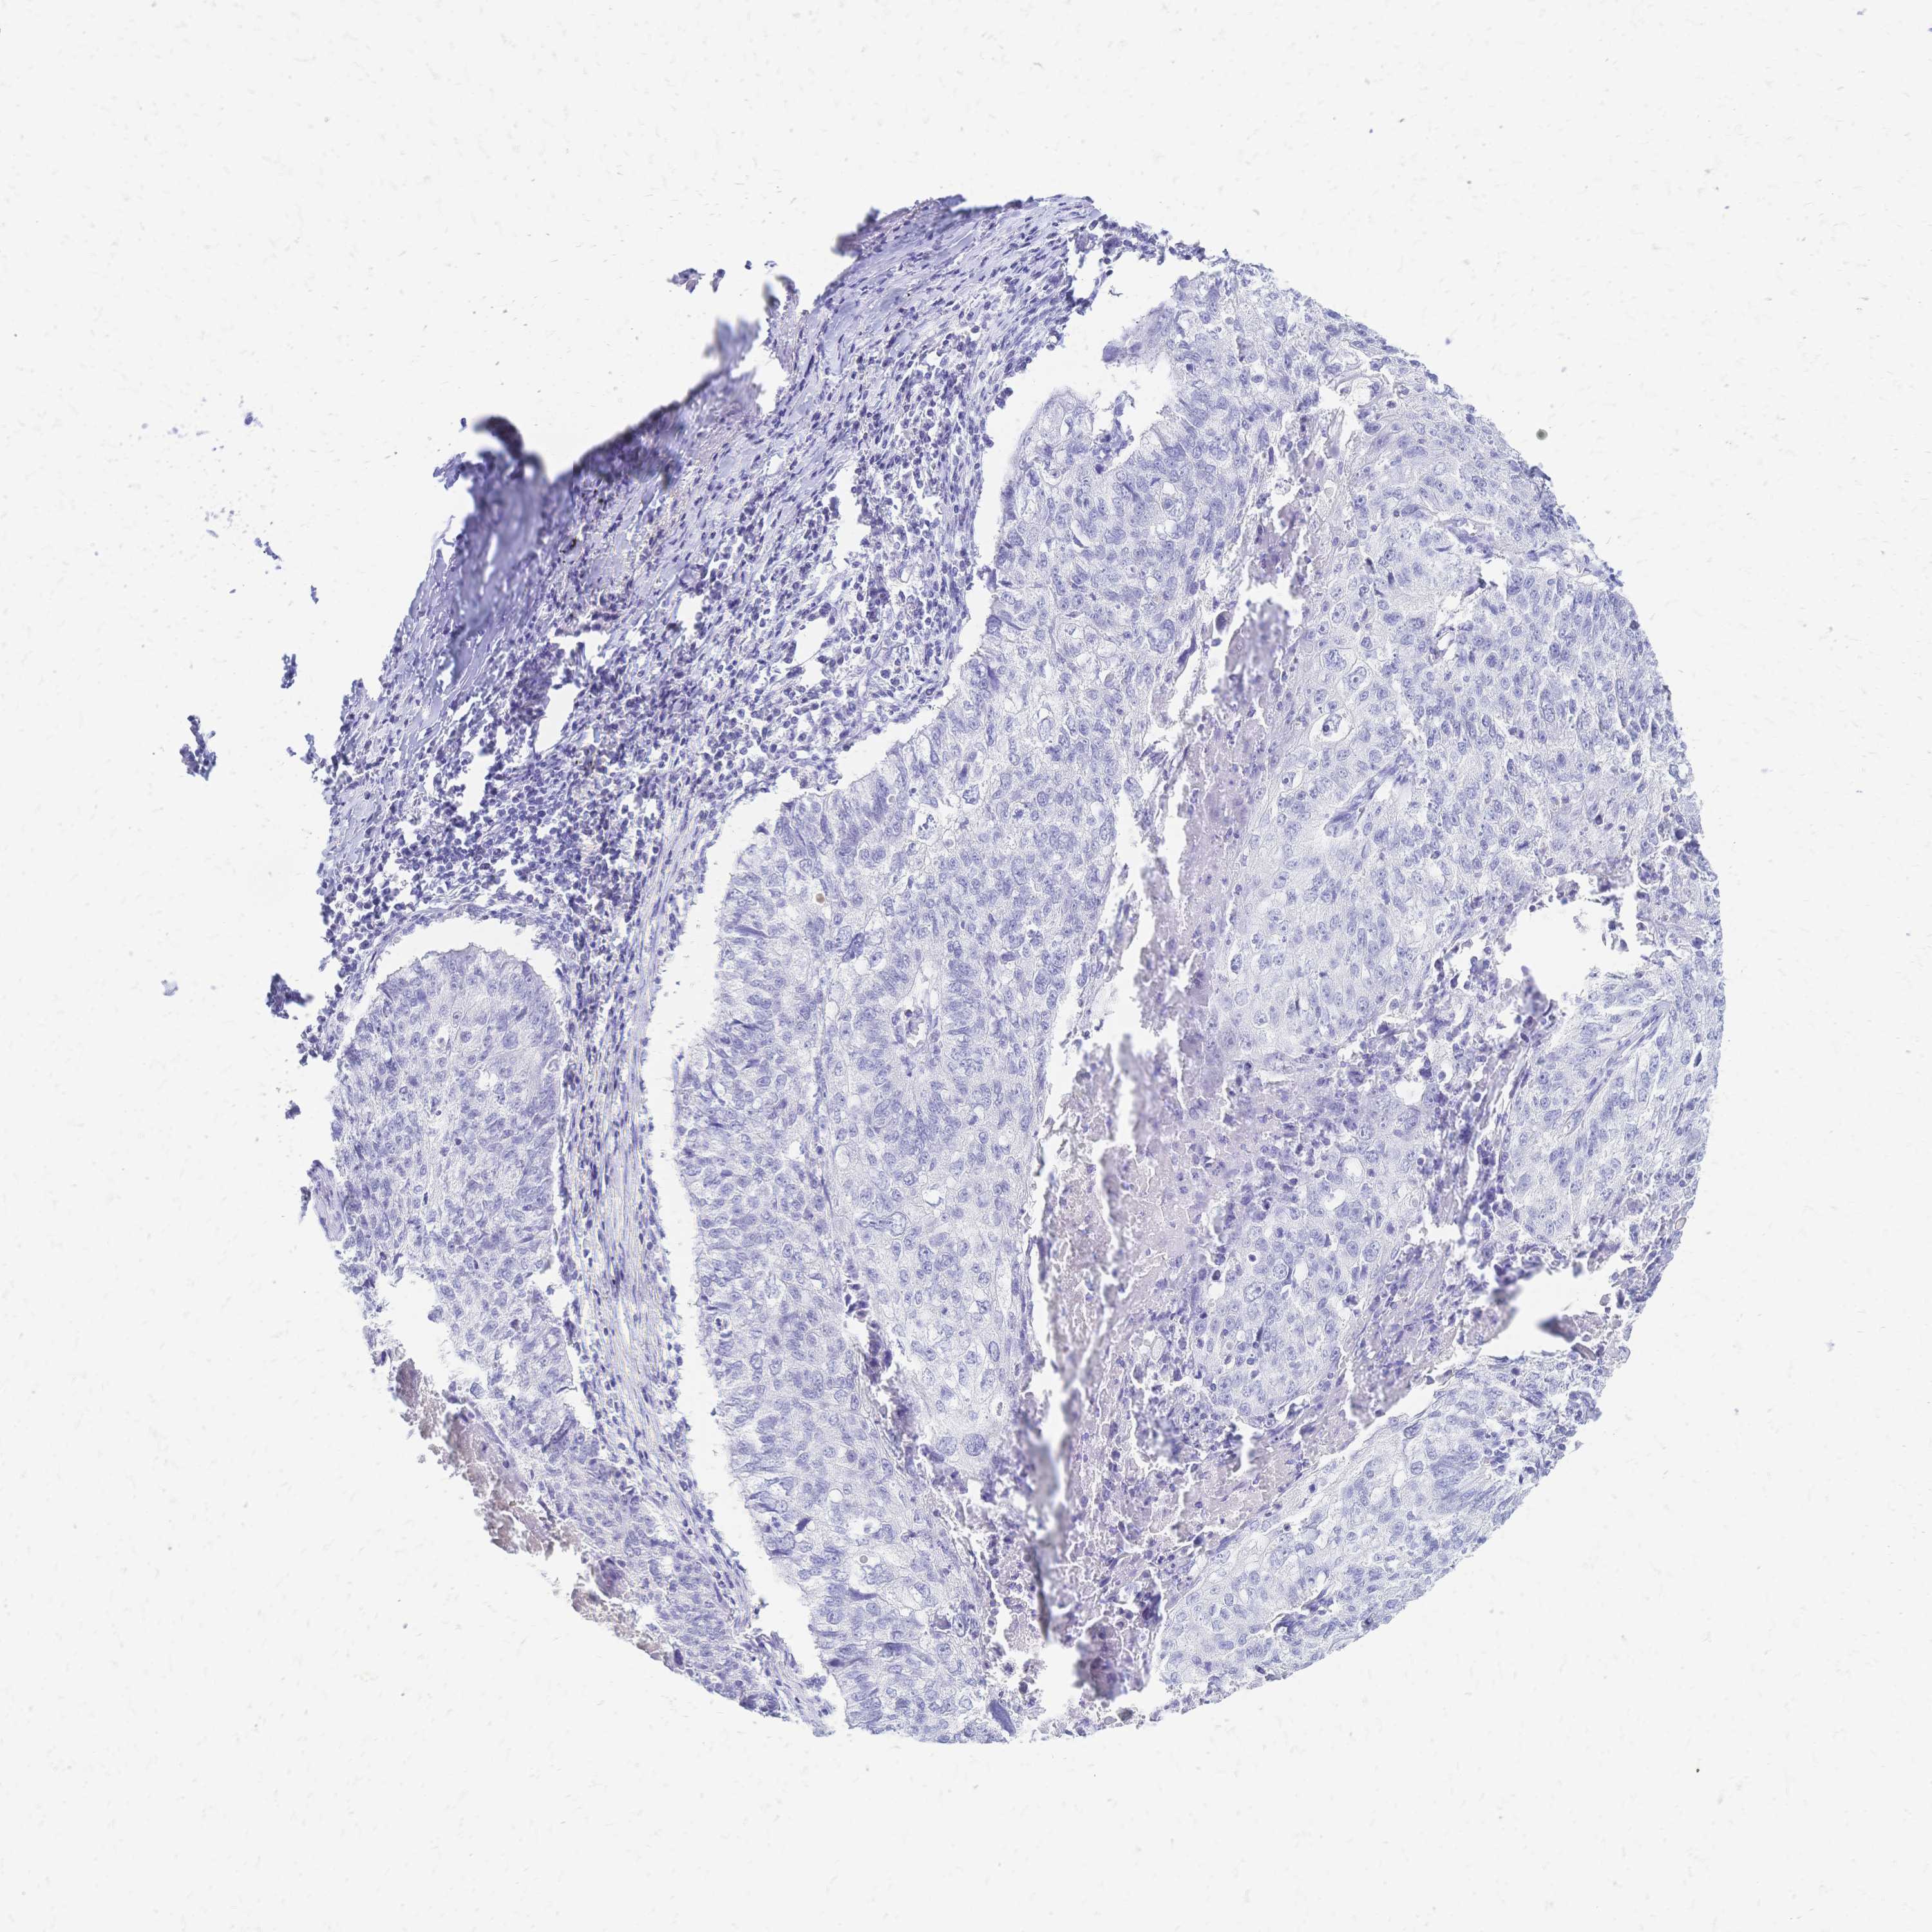

CANCER LUNG CANCER Show tissue menu

LUAD TCGA LUAD VALIDATION LUSC TCGA LUSC VALIDATION PROTEIN LUAD CPTAC PROTEIN LUSC CPTAC PROTEIN EXPRESSION

ANTIBODIES

AND

VALIDATION